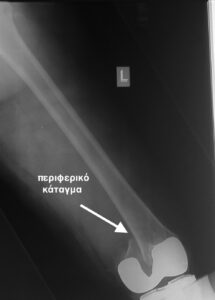

- Περιπροθετικό κάταγμα στην περιοχή του γόνατος , πολύ περιφερικό.

- Η ίδια ασθενής σε profile ακτινογραφία.

- H οστεοσύνθεση με ανάστροφη ενδομυελική ήλωση με πολύ μικρή τομή δέρματος.